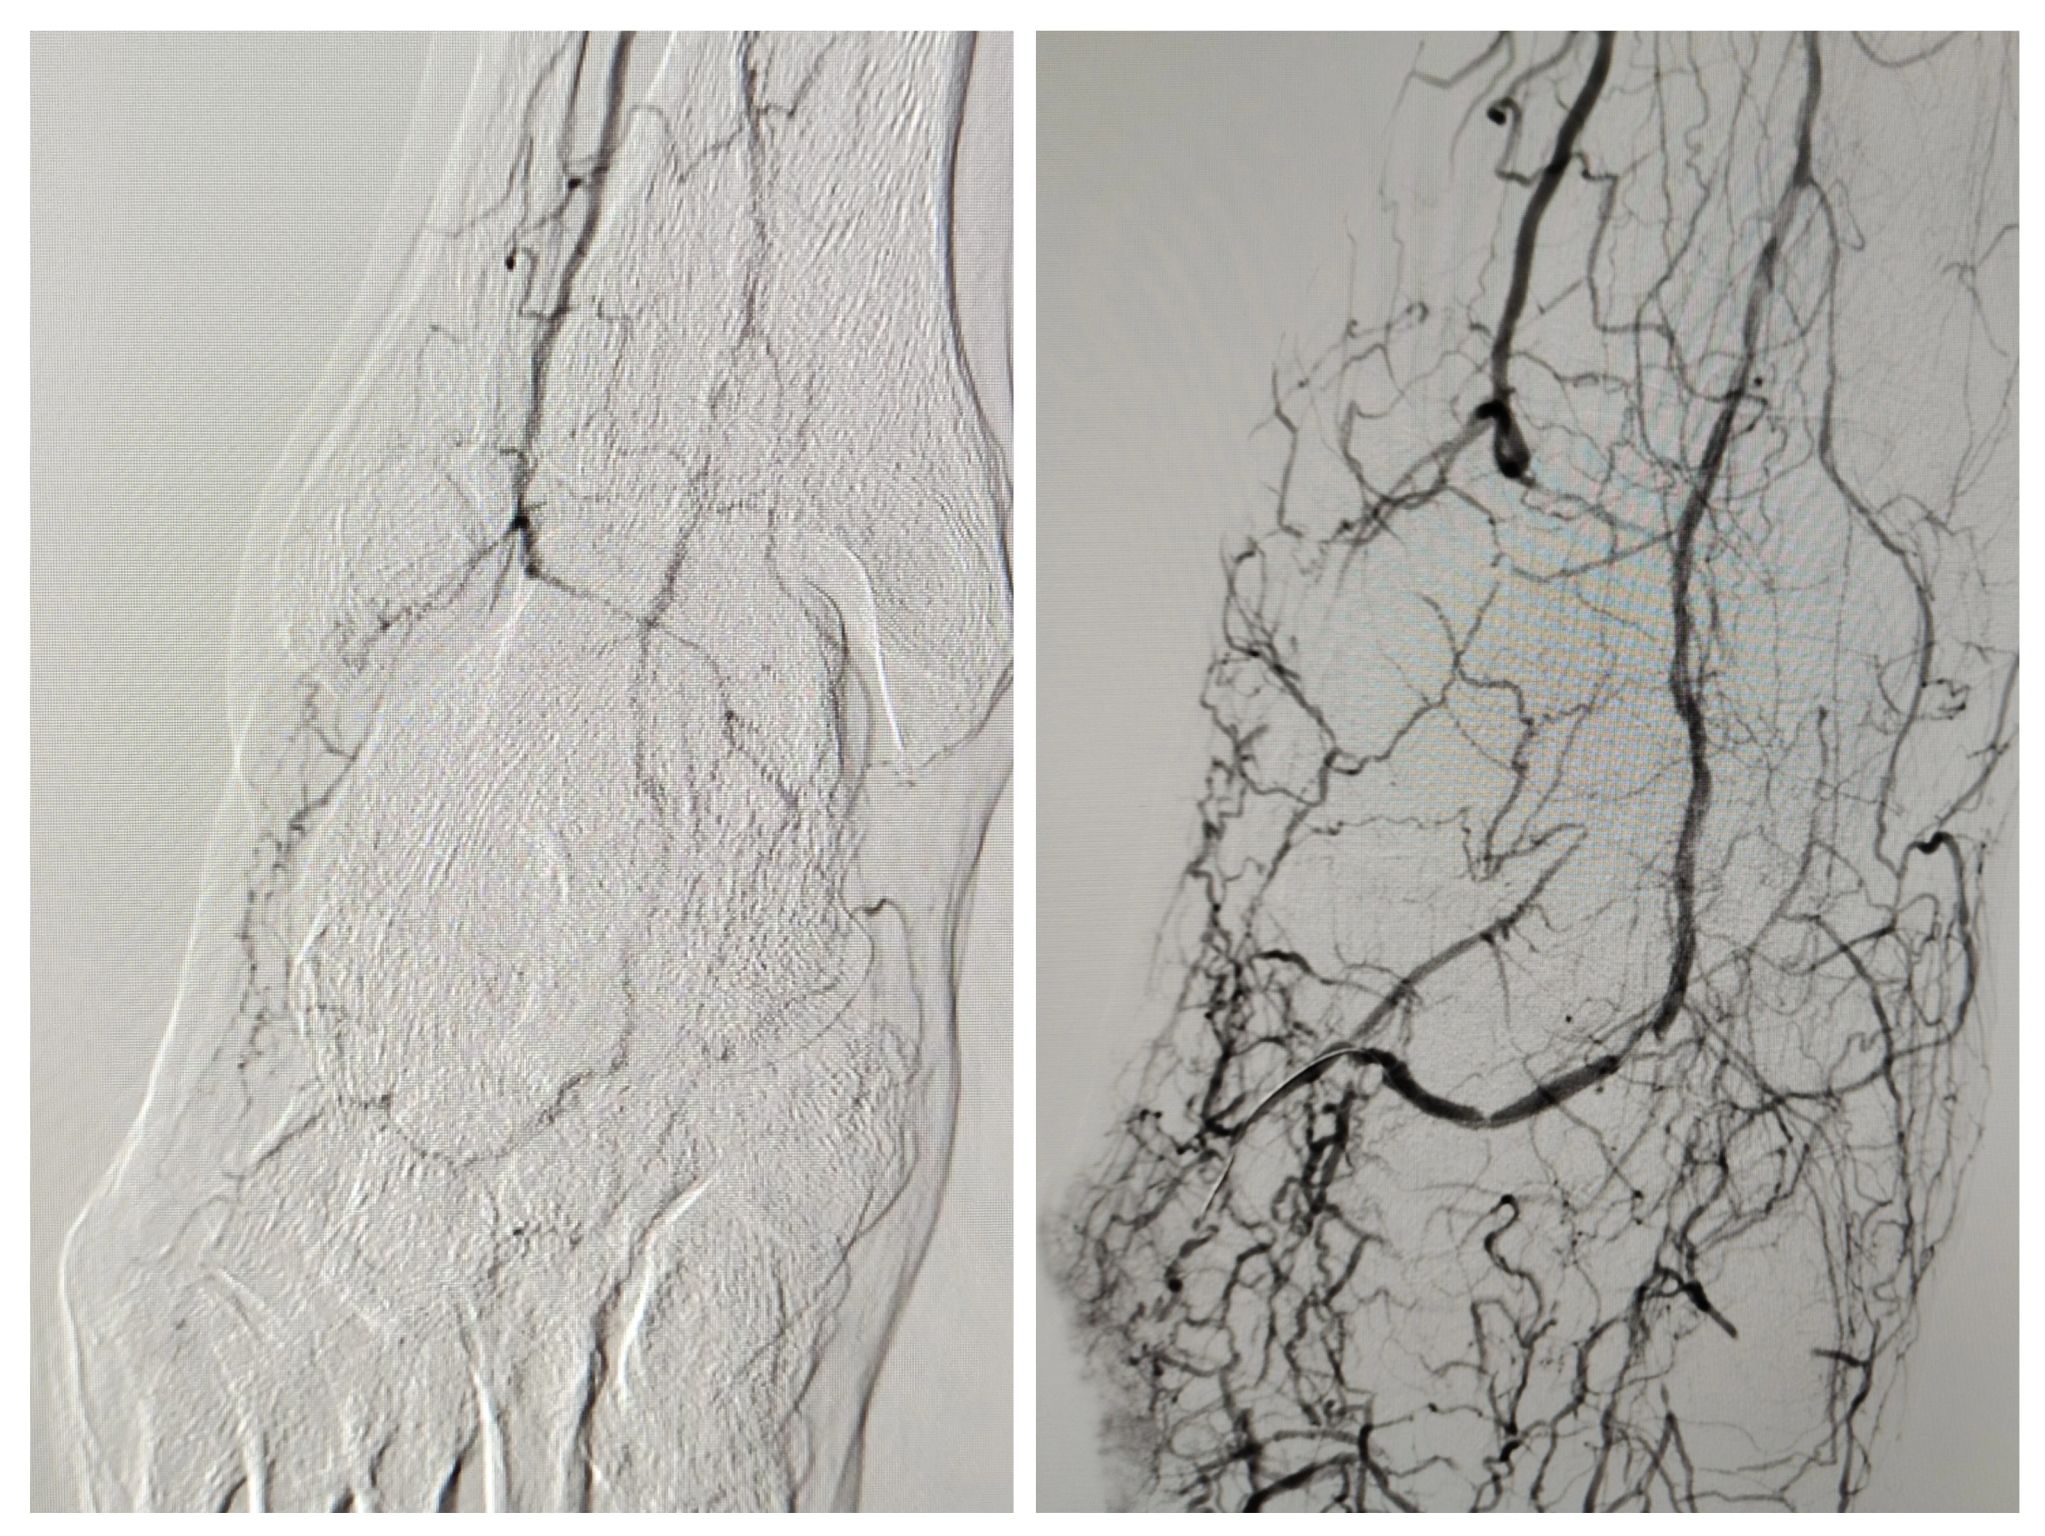

Caso clínico: Revascularización dirigida de un pie diabético complejo

Caso de paciente con diabetes avanzada y enfermedad arterial que acudió por fracaso de injerto y herida isquémica en pie derecho.